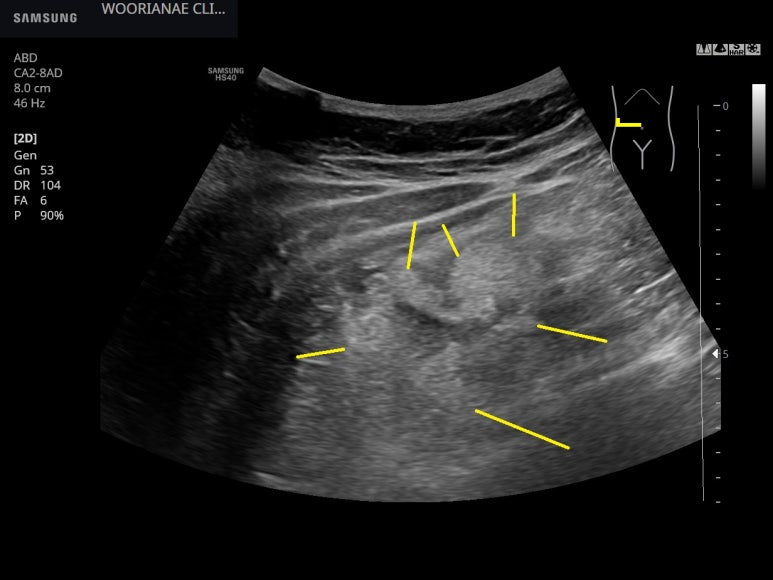

컨벡스 프로브에 염증성 덩어리처럼 이상소견은 잘 보이며...

구별해서 보면 대장 점막하층 비후와 (노란선), 후방감쇄 (빨간선) 가 동반된 게실

게실 주변의 고음영 염증성 지방변화가 가장 두드러지나, 대장을 넘어 내측으로도 있다고 보아도 될듯

게실의 위쪽 염증성 지방변화 모양

위아래의 모습, 약 5 cm 길이의 대장이 영향을 받은 모습

3. cecum 부터 위로 ~ 5 cm 가량 대장점막하층의 비후가 관찰됨

우방 외측으로 fecalith가 동반된 게실이 관찰되며 주변부 염증성 지방변화가 동반됨